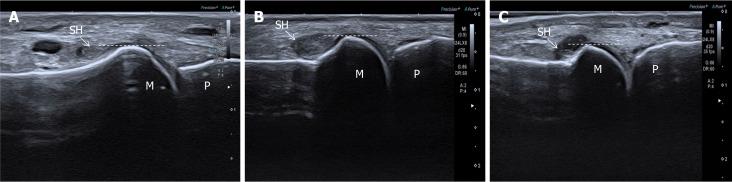

This cross-sectional study included 56 patients (112 MTPJs) with T2DM from Shenzhen Traditional Chinese Medicine Hospital. Synovial hypertrophy was evaluated using a refined semi-quantitative ultrasound grading system focusing on the dorsal recess overlying the metatarsal bone. Serum 25(OH)D levels were measured. Logistic regression and threshold analyses assessed associations between vitamin D status and hypertrophy severity.

Of 112 joints assessed, 98 exhibited synovial hypertrophy (grade 1: 40; grade 2: 50; grade 3: 8). The refined grading system demonstrated strong intra- and inter-observer reliability (intraclass correlation coefficients = 0.79 and 0.73, respectively). Lower serum 25(OH)D (< 24.3 ng/mL) was independently associated with moderate-to-severe hypertrophy [odds ratio (OR) = 0.83; = 0.0163]. Vitamin D deficiency significantly increased the likelihood of moderate-to-severe hypertrophy compared with non-deficiency (OR = 3.86; = 0.0422). Threshold analysis identified 23.8 ng/mL as a critical serum 25(OH)D level, below which each increment reduced moderate-to-severe hypertrophy risk by 21% (OR = 0.79; = 0.0078).